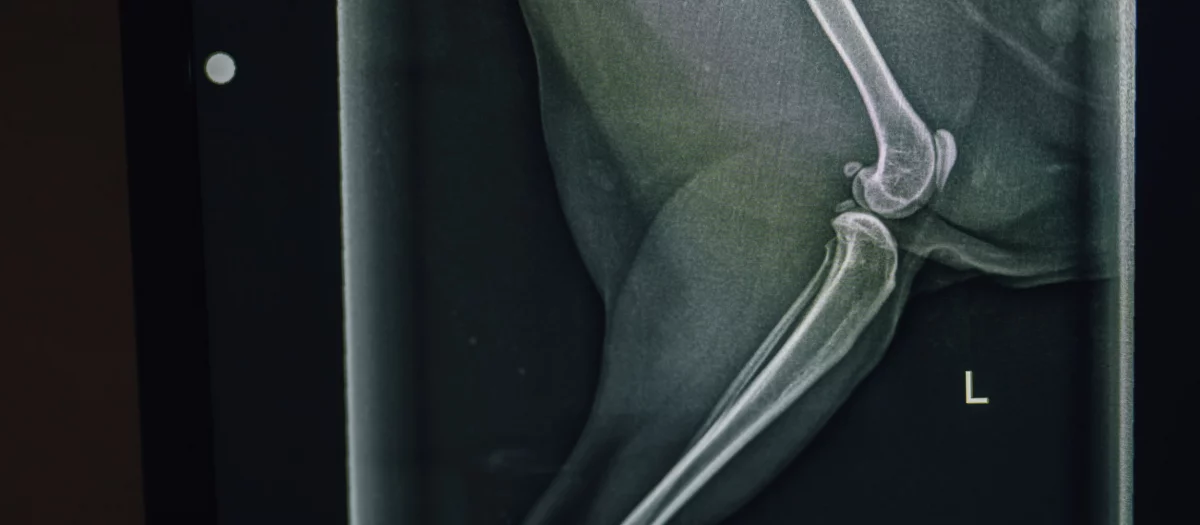

Tiefe Einblicke in kürzester Zeit – mit hochauflösender Computertomographie für dein Tier

Unsere CT-Diagnostik liefert gestochen scharfe 3D-Bilder – für Klarheit bei unklaren Beschwerden.

Wann braucht mein Tier eine CT-Untersuchung?

Eine CT wird eingesetzt, wenn Röntgen oder Ultraschall nicht ausreichen, zum Beispiel bei unklaren Erkrankungen, Verletzungen oder Tumorverdacht.